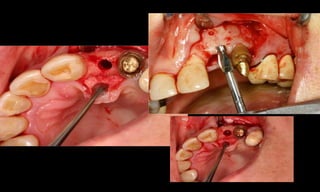

10-10-2005

Novembro de 2005

24-01-2006

Cone Morse